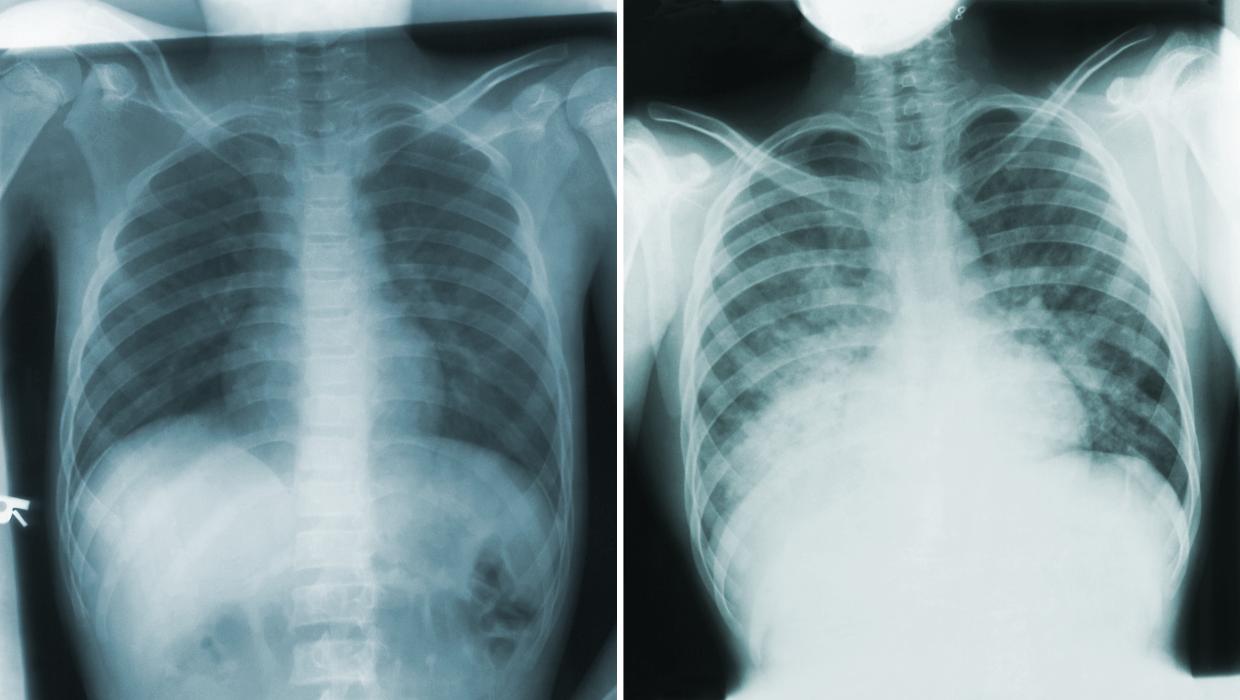

This remark from one of the physicians struck a chord with Porter, highlighting the inefficiencies prevalent in healthcare systems where information is not shared effectively. After a thorough examination, his son was diagnosed with post-viral asthma. The prescribed medications included albuterol, which is referred to as salbutamol in New Zealand. Porter’s familiarity with healthcare terminology helped him navigate this confusion, but it illustrated the dialects within healthcare systems—different terminologies and data formats that create barriers.